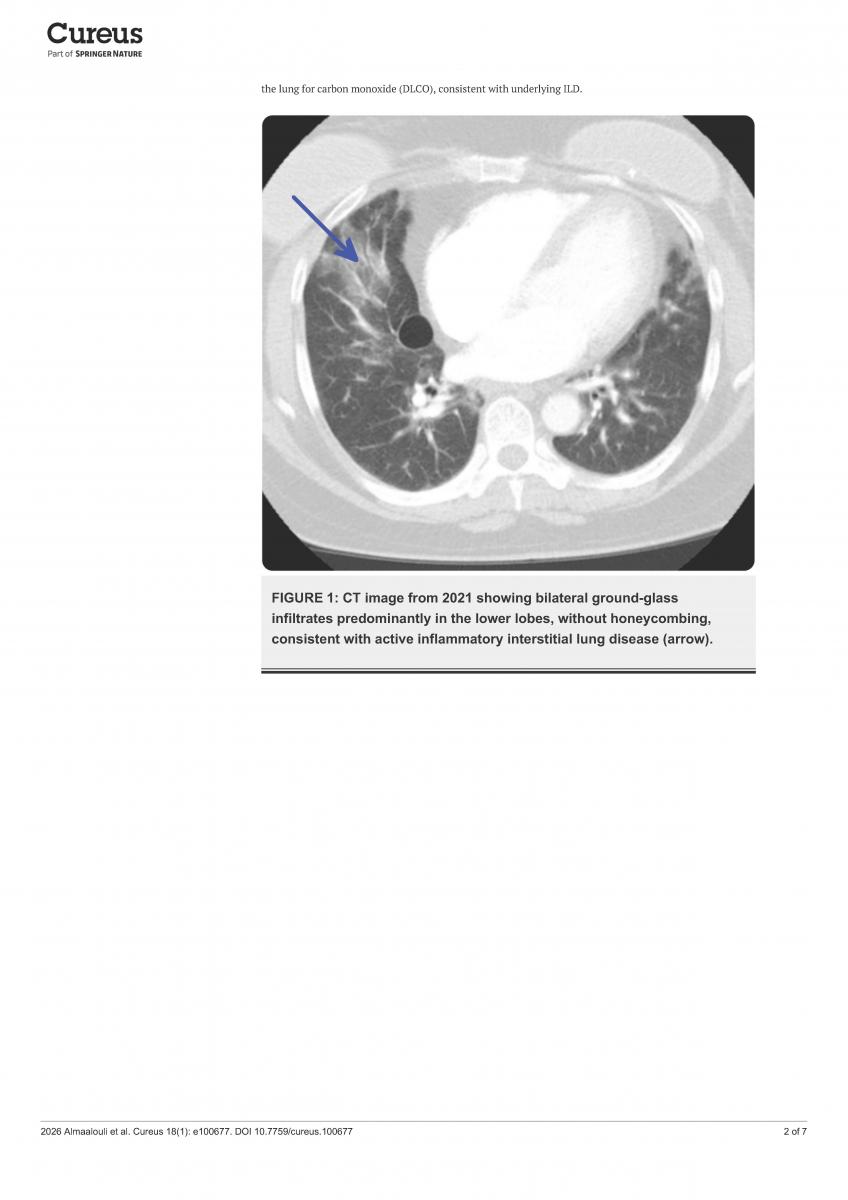

Antisynthetase syndrome (ASS) is a rare autoimmune inflammatory disease. Signs and symptoms include interstitial lung disease, myositis, Raynaud’s phenomenon, joint pain, "mechanic’s hands," and fever. Due to breathing difficulties, the disease is often misdiagnosed as idiopathic pulmonary fibrosis, and delays patients from receiving timely immunosuppressive treatment.